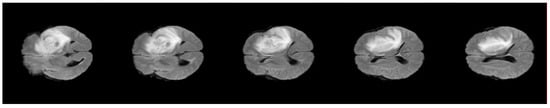

4.3. Experiment 3: Role of DA to Reduce Level Set Iteration

| Methods | Patient No.1 | Patient No.2 | Patient No.3 | Patient No.4 | Patient No.5 |

|---|---|---|---|---|---|

| Level set with DA clustering | 15 | 18 | 16 | 15 | 20 |

| Level set without DA clustering | 252 | 330 | 371 | 266 | 407 |